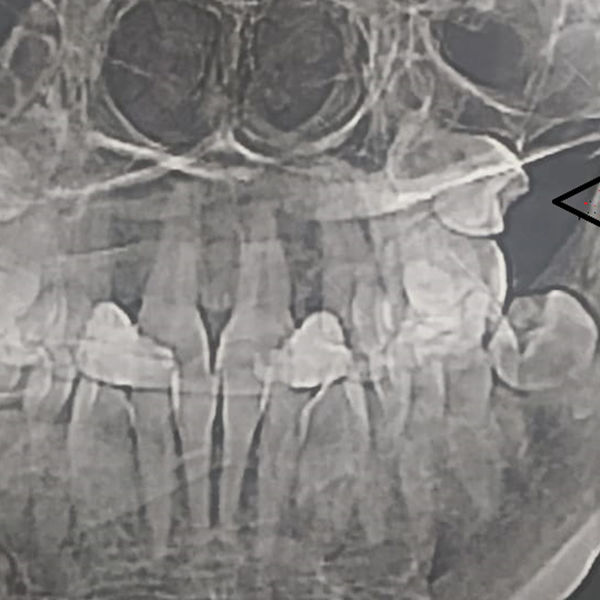

Жительница Самары обнаружила, что в гайморовых пазухах у нее выросли зубы, сообщает ГТРК «Самара».

Об этом женщина узнала, сделав МРТ. Выяснилось, что «четверки» (зубы которые идут после клыков) выросли вместо челюсти в носу.